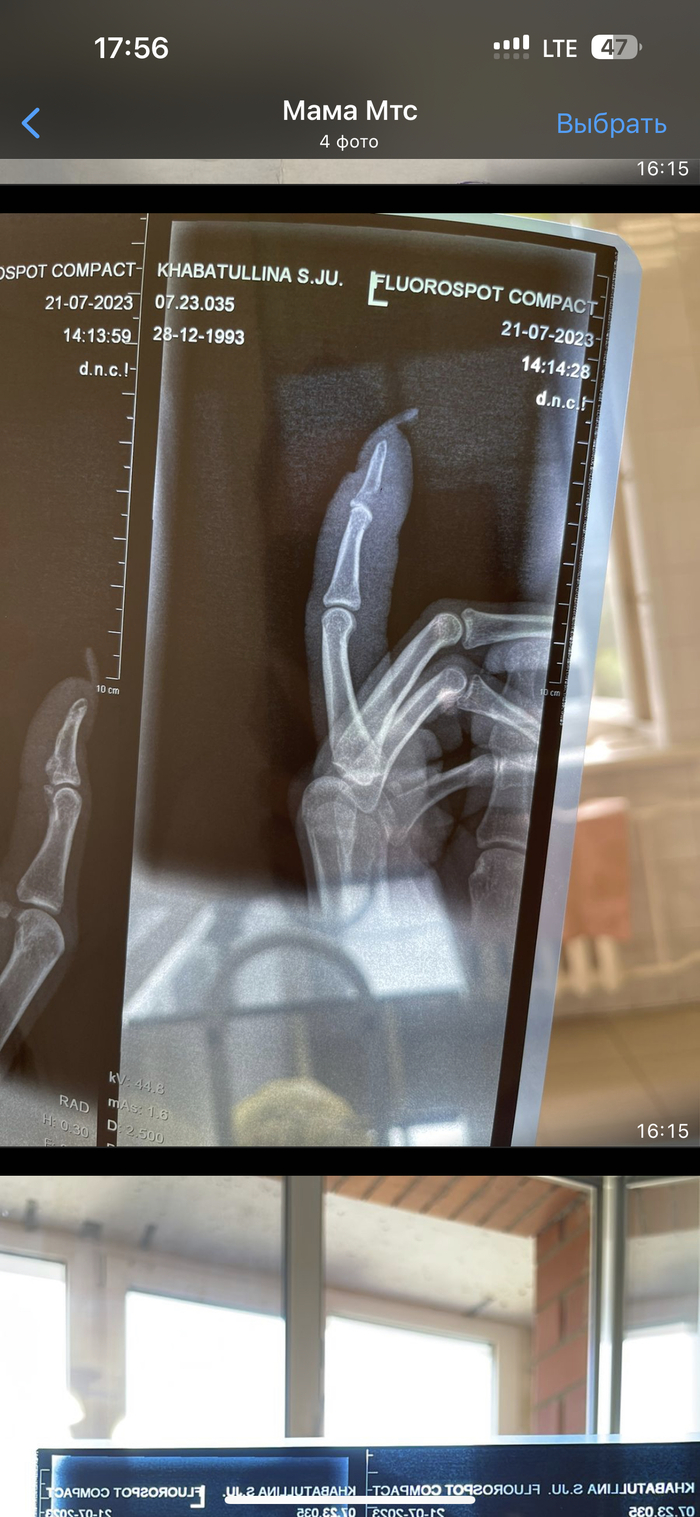

Срочно нужна помощь в Спб или Москве

Здравствуйте! Работаю у вас в области, недавно у младшей сестренки случился инцидент. Ездила отдыхать на Алтай со своим котом. Он сбежал, нашли его в подвале, когда она пыталась его взять он ее укусил за палец. Пошло заражение. В больнице в Иркутске (она там проживает, но сейчас вылетает в питер) сказали что нужно прийти на артем через пару недель, отек сам спадет. На приеме сказали что пошло заражение, нужно отрезать палец по фалангу. Девочка в истерике, скромная и добрая. Проконсультировались час назад с первым врачом с Питера до кого все таки смогли достучатся, сказал что шансы спасти палец есть, но не обещает. Есть снимки , могу отправить. Подскажите люди добрые пожалуйста, есть ли может у кого опыт? Может кто то сможет принять? Это моя сестричка и не могу найти себе места🥺 она мне дорога. Времени мало, через два три дня говорят что пойдет заражение уже на кисть. Прошу помощи 🙏 в обычном штатном режиме записаться иногороднему тем более не знающему города, большая потеря времени, которого остается все меньше. Может есть номера или среди Вас есть человек который может помочь. Пост без рейтинга. Пикабу, первый раз прошу помощи, помощи не для себя, но очень сильно рассчитываю

Показать полностью 4